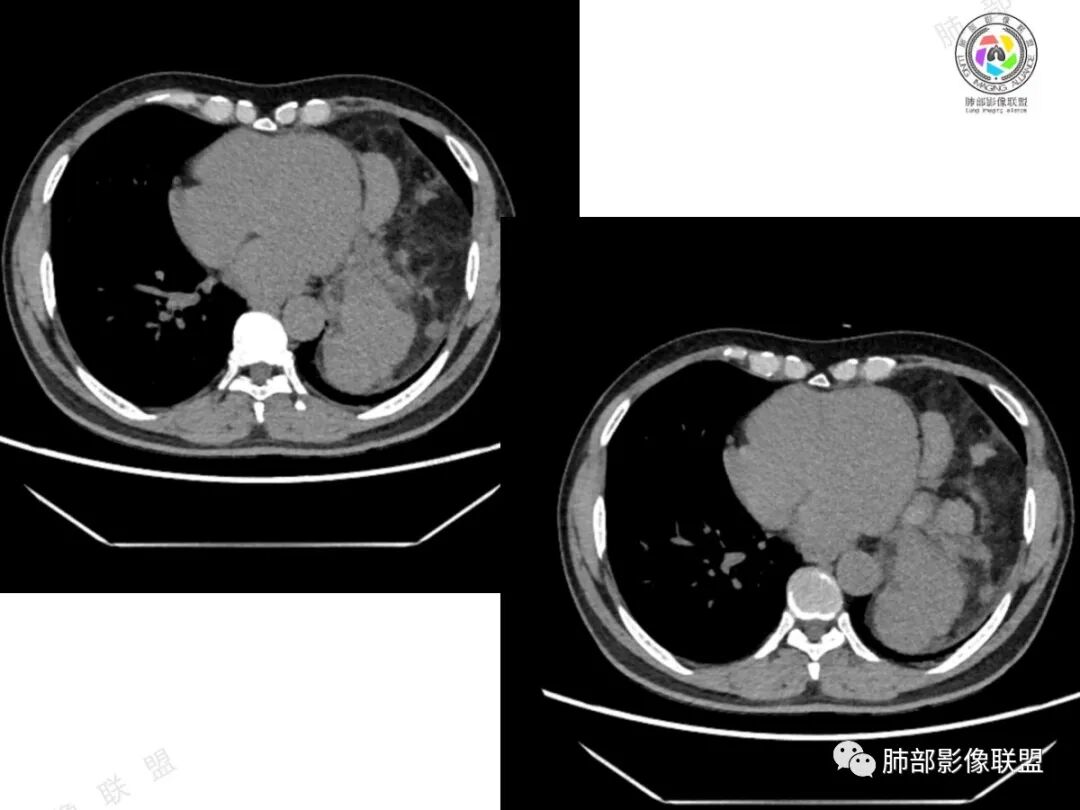

2、影像所见:左侧纵隔紧贴心包铸型生长巨大混杂密度肿块,边界清楚,临近结构受推挤移位,无明显外侵征象。肿块自主动脉弓旁一直顺延到至膈顶,呈“垂乳征”。病灶脂肪成分居多,斑片状、结节状及团块状实性密度成分散落其中,呈地图样分布,实性成分偶见低密度线样分隔,未见明确钙化影。增强扫描实性成分呈延迟明显强化,并见强化血管影。纵隔内有肿大淋巴结,未见胸腔积液,肺内及胸膜未见转移性病灶。

①脂肪肉瘤:本例含较多脂肪组织,需考虑分化成熟型脂肪肉瘤(高分化型)的可能,其好发于前中纵隔的下部及心膈角区,肿块常大,偏于一侧,可有分叶,包膜可完整,与周围组织器官界限清楚。以脂肪密度为主的肿块,增强后仅见间隔或实性部分轻微强化。而本例实性成分过多,且实性病灶强化较明显,与高分化型脂肪肉瘤表现矛盾。

③畸胎瘤:多见于年轻患者,除实体部分的软组织密度、液体部分的水样密度和脂肪组织的脂肪密度外,钙化和骨化较常见,特征性表现是可出现脂肪-液体平面,有时在此界面出现线状及条索状混杂密度影为毛发团。成熟囊性畸胎瘤由分化成熟的组织构成,可以只有脂肪和囊变或者只有囊变。本例年龄较大,未见明确钙化及骨化,畸胎瘤似乎缺乏影像学证据。